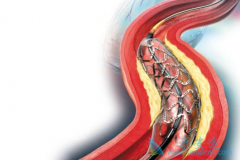

心脏支架作为现代心血管医学发展中的一个里程碑,确实在冠心病的治疗中发挥着非常重要的价值。 生物可降解支架 给冠心病介入治疗带来了新的革命。但是生物可降解支架真的能成为心血管患者的福音吗?目前心脏支架主要分为不可降解支架和完全降解支架两个 ...

生物可降解支架 安全吗?其实早在20世纪90年代初,就已经提出生物可降解支架的概念,但发展没有金属裸支架和药物洗脱支架快,最终被药物洗脱支架所替代。目前药物洗脱支架长期随访发现潜在的支架内血栓风险,最近10余年生物可降解支架科技和材料学取得 ...

为了改善冠心病介入治疗短期和长期的疗效与安全性,所以研发了支架。第一代支架是金属裸支架,使冠心病介入治疗前进了一大步,使介入治疗变得非常安全,当血管发生严重狭窄时单纯球囊扩张预处理后,再用支架把血管完全撑开,就能解除心肌缺血危险,而且 ...